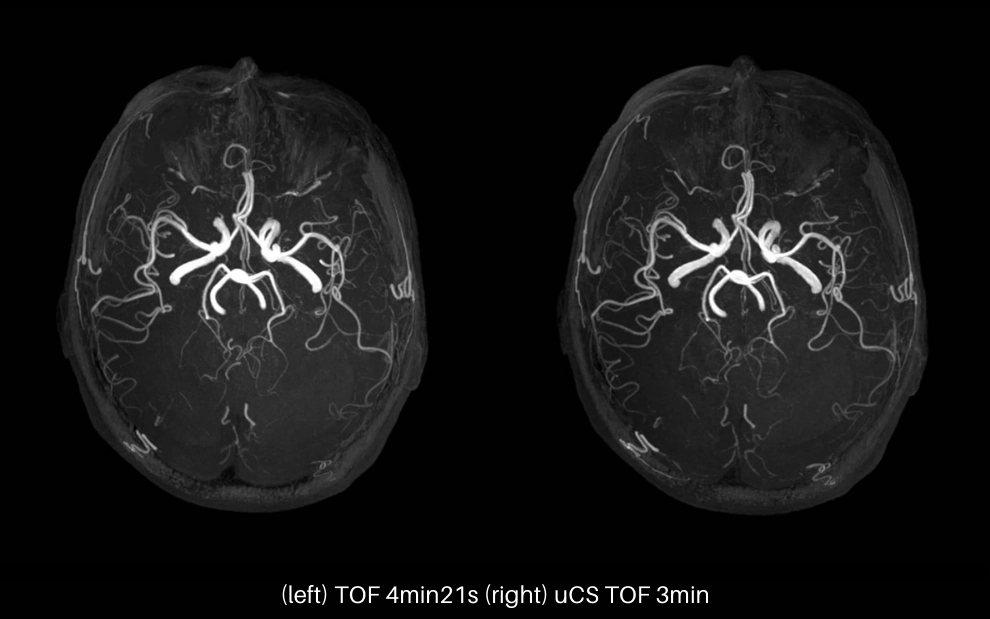

uCS High Spatial Resolution

Static scan with uCS can achieve an acceleration factor of 6 or above in the spatial domain, which allows faster acquisition of high-resolution 3D imaging as well as high detectability for small lesions.